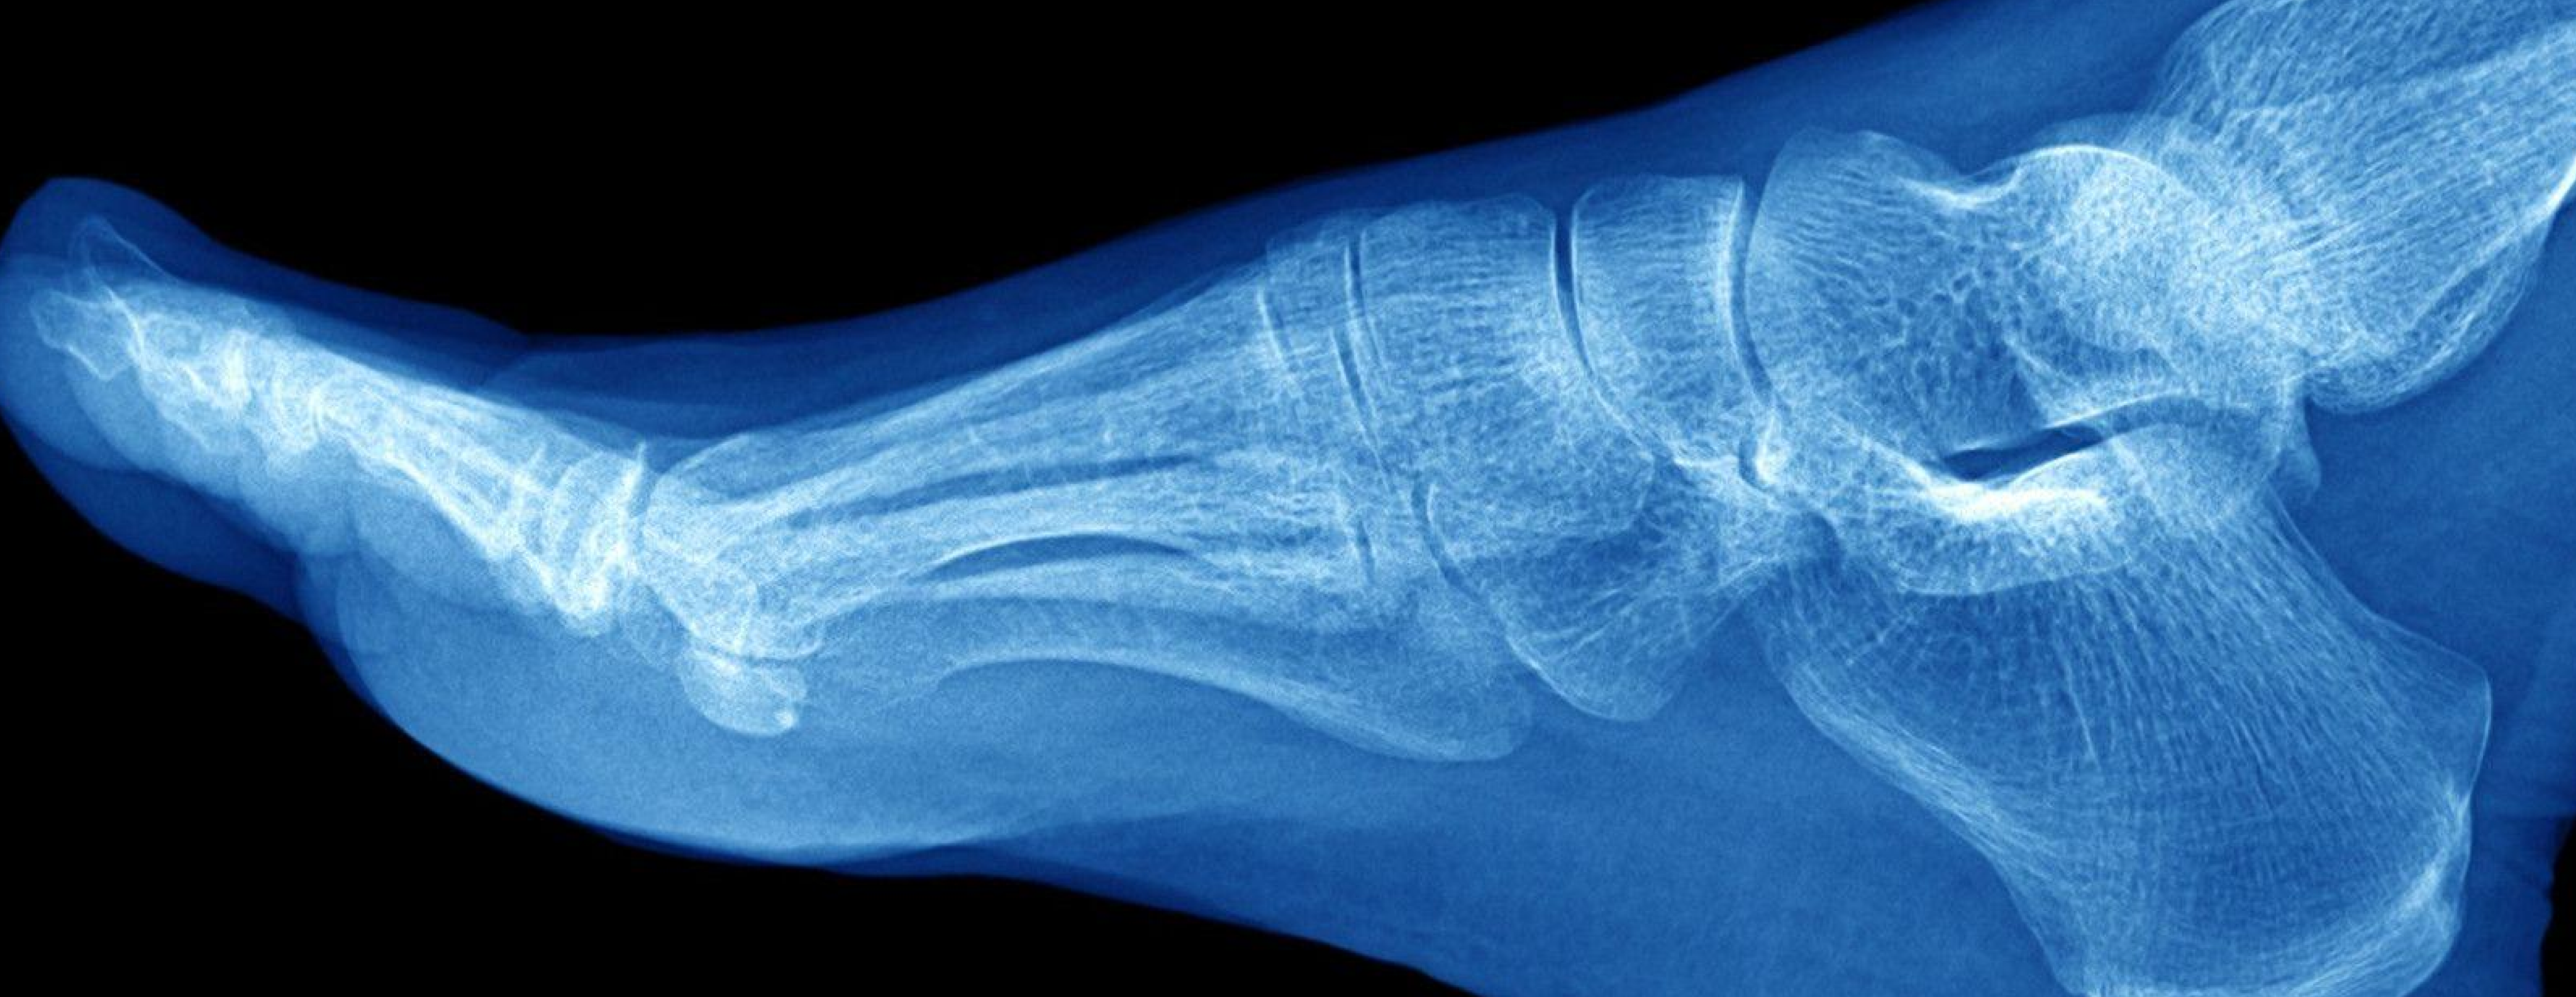

Your feet and ankles carry the entire weight of your body every single day. They keep you balanced, stable, and mobile — whether you’re walking, running, or standing still. When pain, swelling, or injury affects this area, it can make even the simplest movement difficult. At Dr. Anoop Mohan Nair’s Orthopedic Clinic in Ranchi, we offer comprehensive diagnosis and treatment for all foot and ankle problems, from minor sprains to complex fractures and deformities.

The foot and ankle together form a highly complex structure made up of 26 bones, 33 joints, and more than 100 ligaments, tendons, and muscles.

Because of this complexity, even a small injury can cause major discomfort and affect your posture and gait.

At our clinic, every case is carefully evaluated with clinical examination, digital X-rays, or MRI to understand the exact cause of the problem before starting treatment.